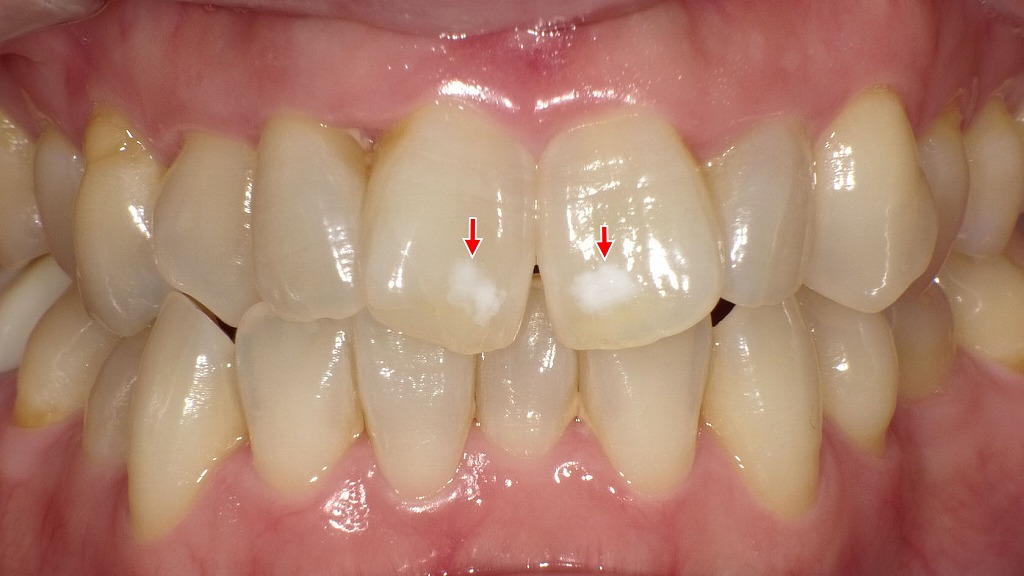

1枚目の画像:術前

1枚目の画像では、エナメル質形成不全によるホワイトスポットが確認できます。特に左上の中切歯(前歯の中央右側)に明瞭な白濁が見られ、隣接する側切歯や犬歯にも白い不透明な部分が点在しています。

2枚目の画像:ホワイトニング後

2枚目の画像では、ホワイトニング処置後の状態です。歯全体の色調がやや明るくなり、周囲とのコントラストが緩和されたことで、ホワイトスポットがわずかに改善し、以前より目立たなくなっています。完全に消失したわけではありませんが、自然な色のなじみが得られています。